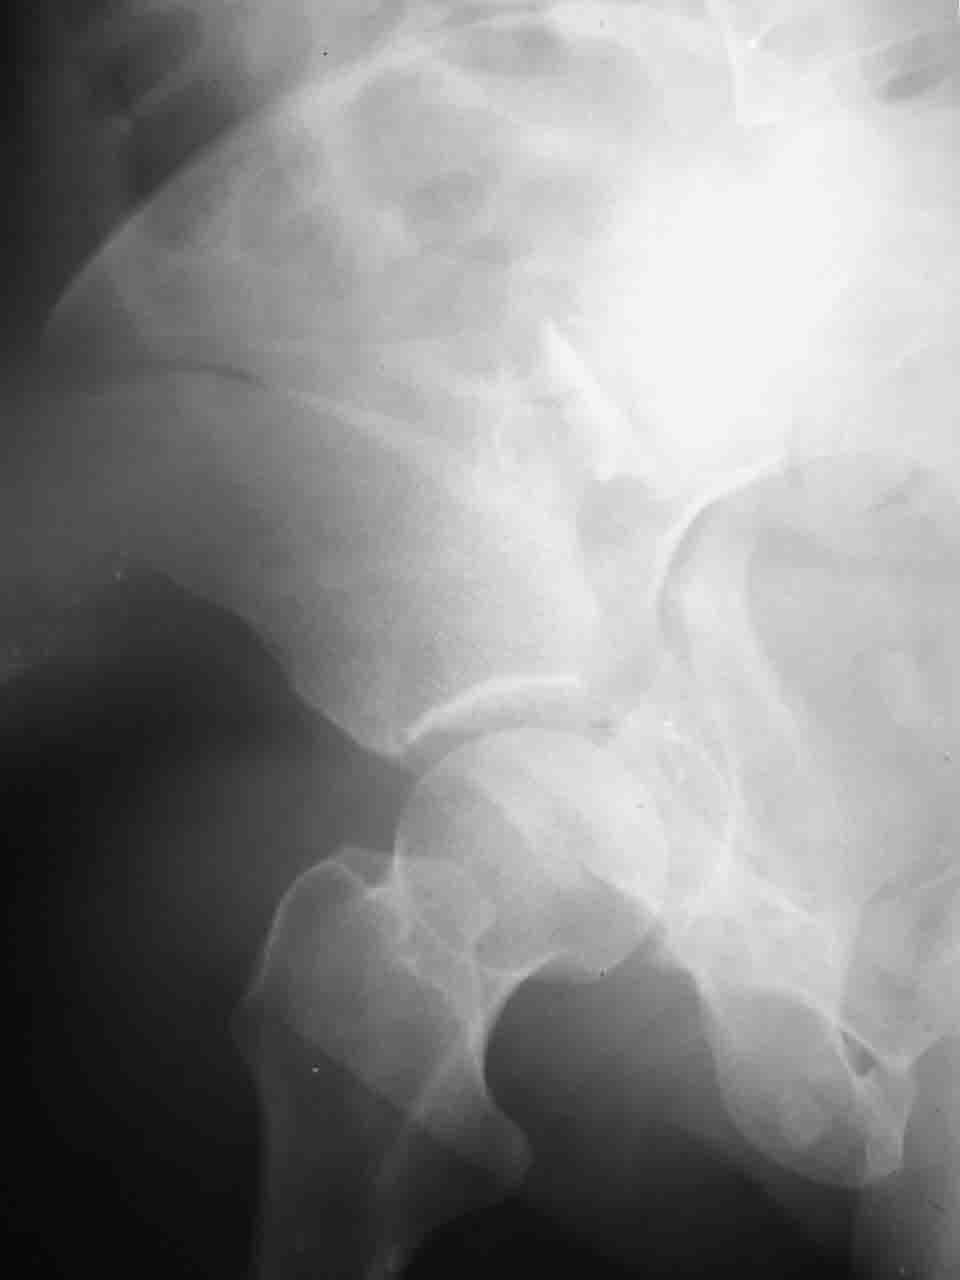

Re: Перелом вертлужной впадины

Снимки и схема